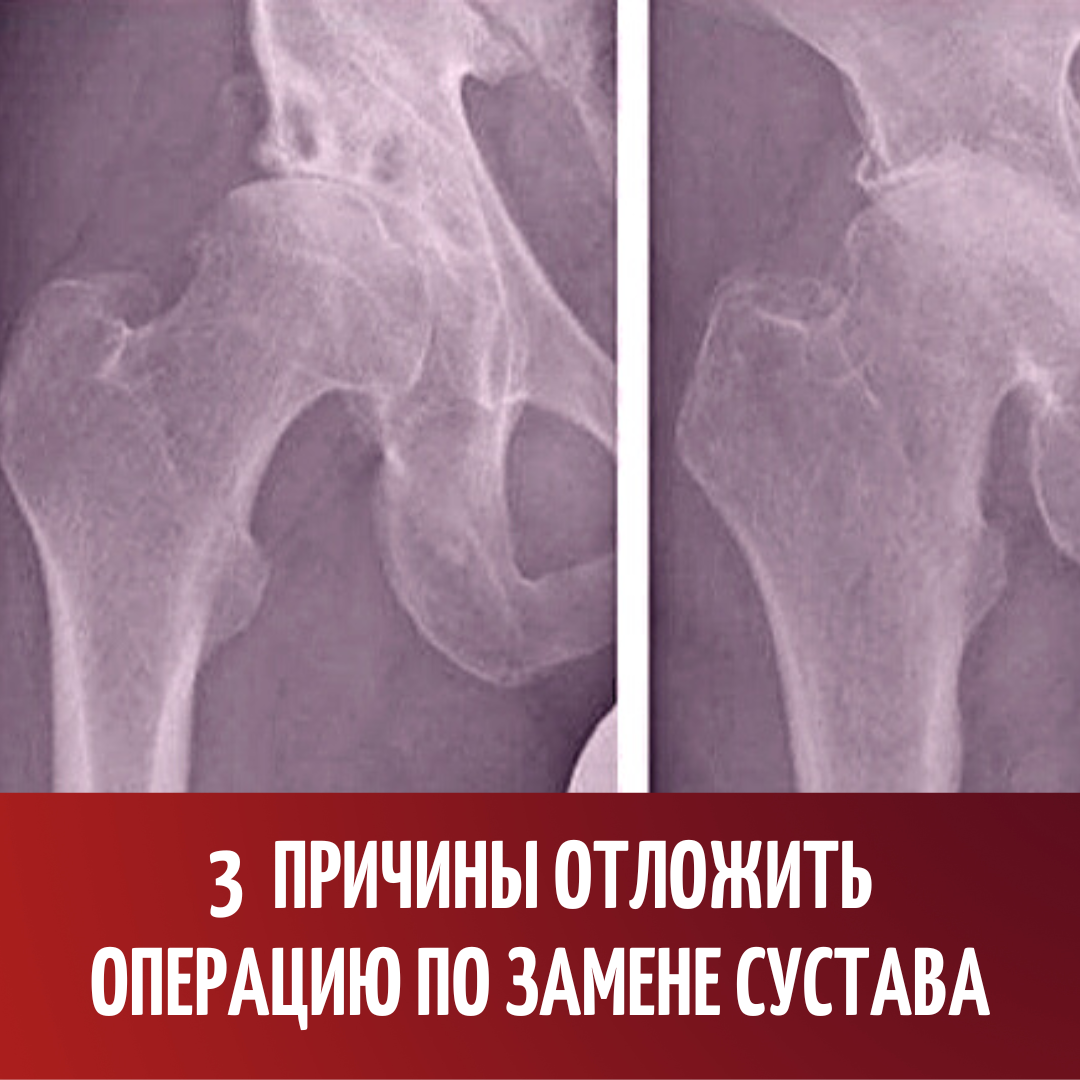

3 причины отложить операцию по замене сустава. Артроз